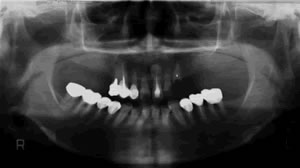

私は歯科医師として患者様にいろいろな治療の選択肢をご提供できるように常に努力をしていきたいと考えており、 インプラント治療はその選択肢の一つだと思います。当院ではより正確に、安全にインプラント手術が行えるようにCTスキャンを応用した診断法を1996年から始めました。 CTスキャンは通常は大きな医科の病院にしか設置されていません。 以前はそういった病院に患者様に行ってもらい撮影をしておりました。 しかし現在では歯科用のCTスキャンが開発され、当院にも2008年4月にプレヴィスタと言うコーンビームCTが設置されました。これによりインプラントのCT撮影、手術シュミレーション検査がいつでもできるようになりました。 難症例を除き、撮影後少しお待ちいただければインプラント治療が可能かどうかご説明できます。患者様もこのCT画像をご覧になると、インプラント治療がどのようなものか良くわかると思います。インプラント治療に関心のある方はお気軽にご相談ください。